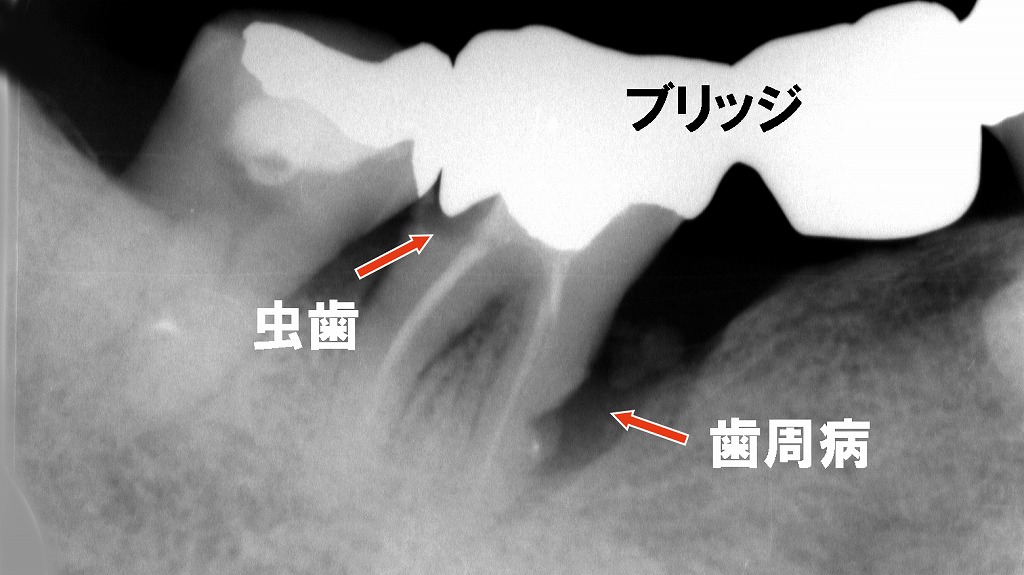

このX線画像は、下顎の5番・6番・7番に装着されたブリッジの状態を示しています。以下のような問題点が確認できます。

🦷 ブリッジの構造

5番から7番の3本で連結されたブリッジが確認されます。中央の6番部が欠損しており、5番と7番が支台歯(ブリッジを支える歯)として使用されています。

⚫ 7番の近心側:歯槽骨吸収(歯周病)

7番の根の近心側(前方側)に、明らかな歯槽骨の吸収が認められます。

この所見は歯周病の進行を示唆しており、炎症によって歯を支える骨が減少している状態です。

歯根の周囲に黒い透過像(骨の密度低下)が見えるのが特徴です。

🦠 7番の歯冠内:二次う蝕(虫歯)

7番の歯冠部内部に**透過像(黒い影)が確認でき、これは金属修復物の下で進行した虫歯(二次カリエス)**と考えられます。

ブリッジ下では清掃が難しく、セメントの劣化などにより細菌が侵入して虫歯が発生することがあります。

💡 臨床的な懸念点

- 支台歯である7番の歯周支持組織の喪失により、ブリッジ全体の長期安定性が低下しています。

- 同部の虫歯進行により、再製作が必要となる可能性があります。

- 歯周病が進行すると、ブリッジ全体の動揺や脱落リスクも高まります。

✅ 対応の目安

- **歯周治療(スケーリング・ルートプレーニング)**による炎症の改善

- ブリッジの再評価・再設計(場合によっては分割抜歯やインプラント併用も検討)

- う蝕部分の除去と再修復の検討